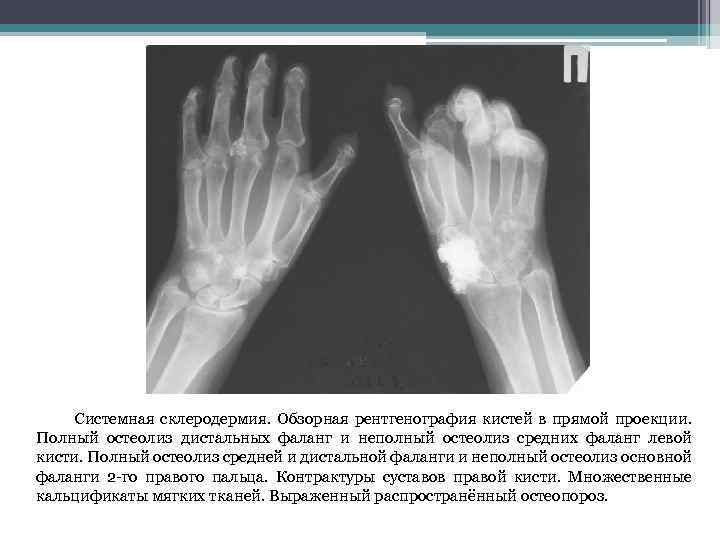

Поражение суставов и костей Полиартралгии и утренняя скованность – частые проявления ССД Акроостеолиз – резорбция концевых отделов дистальных фаланг кистей, вследствие длительной ишемии, проявляется укорочением и деформацией пальцев. Симптом трения сухожилий – крепитация при сгибательных и разгибательных движениях пальцев и кистей. Сгибательные контрактуры – локальное уплотнение кожи и сухожилий. Рука приобретает вид «птичьей лапы»

Системная склеродермия. Обзорная рентгенография кистей в прямой проекции. Полный остеолиз дистальных фаланг и неполный остеолиз средних фаланг левой кисти. Полный остеолиз средней и дистальной фаланги и неполный остеолиз основной фаланги 2 -го правого пальца. Контрактуры суставов правой кисти. Множественные кальцификаты мягких тканей. Выраженный распространённый остеопороз.